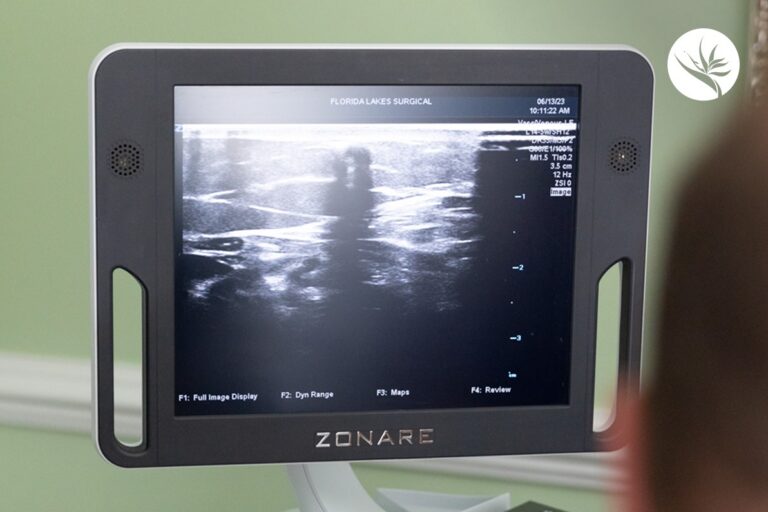

Before recommending any treatments, your vein specialist in Venice will use ultrasound technology to view the soft tissue and blood vessels in your affected area. This gives a clear look at the problem for a fast and accurate diagnosis.